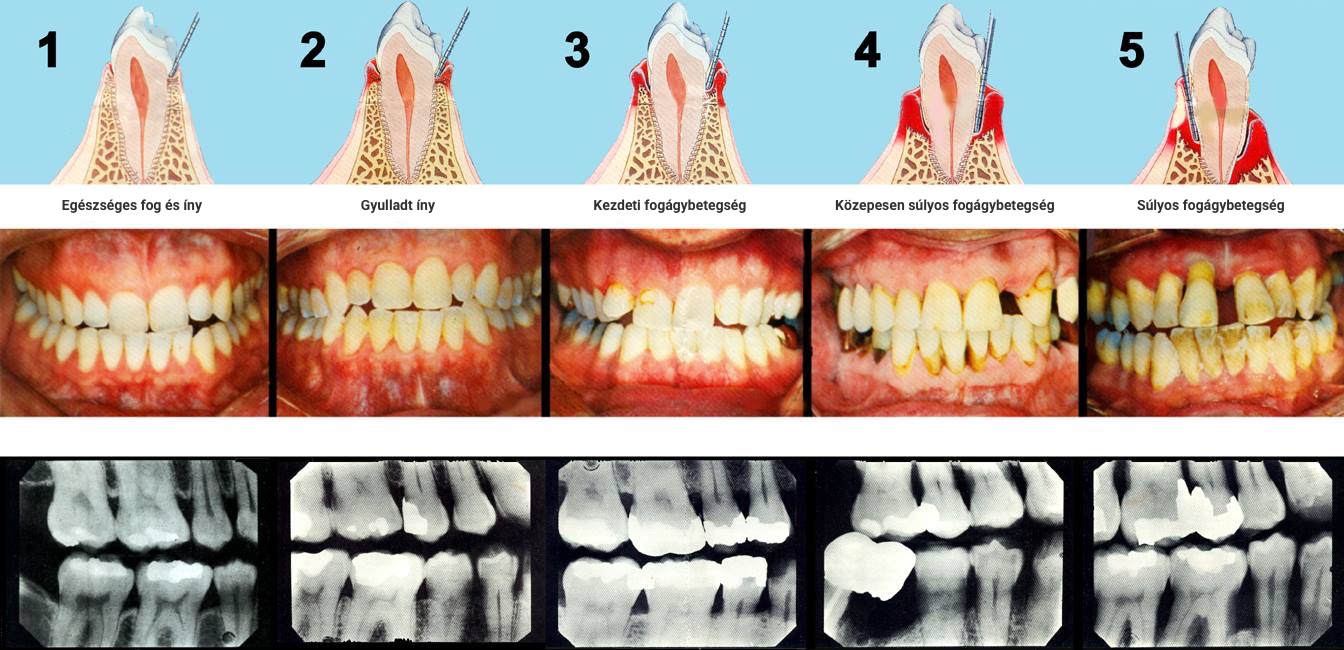

A fogágybetegségben szenvedő páciensek kezelése összetett feladat. Az első találkozás alkalmával betegség súlyosságát, a talált elváltozás esetleges okait vizsgáljuk meg. Számos esetben a páciensek a betegség előrehaladott stádiumában kerülnek szakemberhez, ezért a fogágy tisztítását megelőzően, vagy azzal egy időben szükségessé válhat a már reménytelen fogak eltávolítása. Ilyen esetekben ideiglenes pótlással állítjuk helyre az esztétikát és rágófunkciót.

A szájüregi tüneteken túl, a fogágybetegség hatással van a szervezet más területeire is. Ma már több klinikai tanulmány kimutatta hogy a fogágybetegség fontos szerepet játszik a miokardiális infarktus kialakulásában, cukorbetegségben, valamint alacsony születési súlyt, és koraszülést eredményezhet.